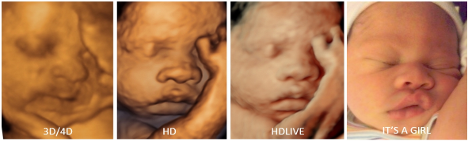

Dok 3D ultrazvuk daje statičan prostorni prikaz, 4D ultrazvuk omogućava trodimenzionalni prikaz u realnom vremenu, dok 5D tehnologija dodatno unapređuje kvalitet slike kroz automatsku optimizaciju kontrasta, dubine i definicije ivica.

Ove tehnologije omogućavaju izuzetno detaljan prikaz anatomskih struktura, posebno mekih tkiva, te se najčešće koriste u prenatalnoj dijagnostici, ali i u procjeni složenih anatomskih odnosa u drugim oblastima medicine.